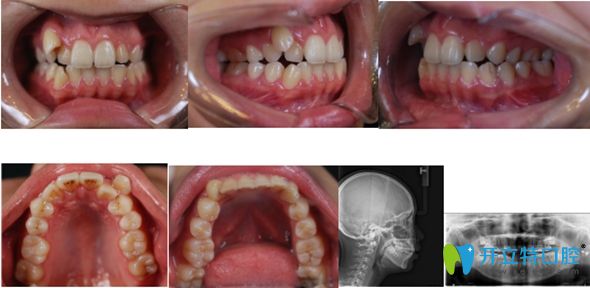

網(wǎng)紅小哥哥在佳美口腔矯正前的牙齒照

<讓小哥哥一直很傷腦筋的亂牙圖>   ↑ ↑